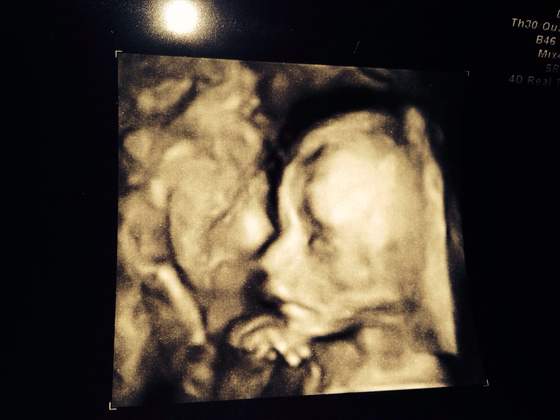

Melduje sie i ja po usg polowkowym. Z malutka wszystko dobrze, wszystkie parametry w normie. Dołączam foto tyle ze robione z tel ale widac

Zobacz załącznik 599439

Słodzinka! Jak dobrze widać twarzyczkę, super żę wszystko okej!